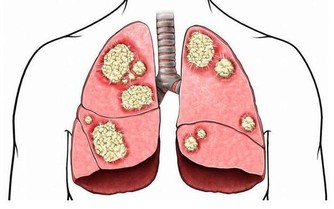

足癬是一種接觸傳染性皮膚病。如果接觸了帶真菌的腳、鞋襪、拖鞋、毛巾和水等,真菌數量比較多,毒力比較強,接觸者的皮膚又比較潮濕,就容易被傳染。

例如,商場試衣間裡的試裝鞋、健身房的公共拖鞋、足療中心的拖鞋和設備等,都是感染腳氣的重要途徑。